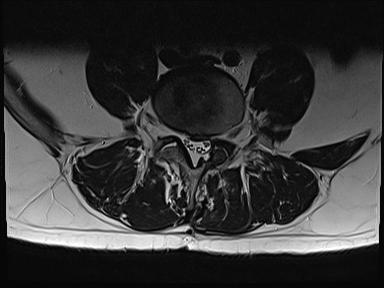

Ich werde mal 2 Bilder der MRT Untersuchung hochladen.

Heutiges MRT ergab das die Bandscheibe immer noch soweit raus ist wie vor 2 Monaten. Also ist nicht weiter gerutscht. Das Narbengewebe ist nur noch schwach auf Kontrasmittel ansprechbar was bedeutet das der Heilungsprozess noch nicht abgeschlossen ist. Einen richtigen berricht bekomme ich erst am montag leider.

Die Ncs können sich nicht ganz erklären wieso es so ist bei mir aber dad die bamdscheibe schon ganzschön raus ist aber noch genug liquorwasser da ist das die cauda Fasern frei schwimmen.

Narbengewebe ist da und umschließt den dura Sack was dazu führt das de4 nerven Strang nicht ausweichen kann....